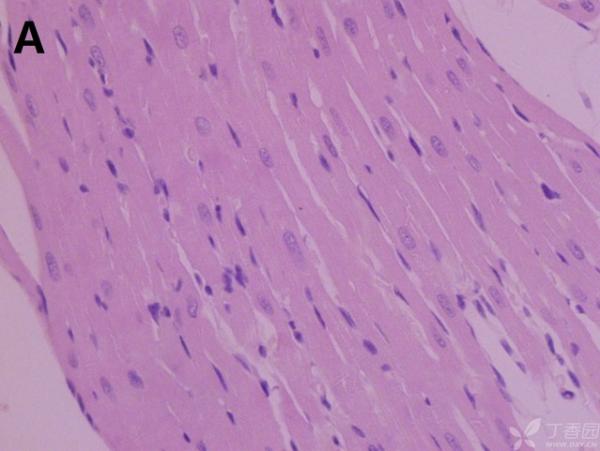

ÎÒ½«Ã¿¸ö×éÖ¯ÅÄÁË3¸öÊÓÒ°£¬ÒÔ±ã×ۺϷÖÎö£¬Âé·³¸÷λ°ïÎÒ°ÑA¡¢B¡¢C¡¢D¡¢E¡¢F¡¢GµÄËðÉË´óСÅŸö˳Ðò ÔÙ°ÑA¡¢B¡¢C¡¢H¡¢I¡¢JËðÉ˵ÄÑÏÖØ³Ì¶ÈÅŸöÐò¡£¸ÃÎÊÌâÒ²ÔÚ¶¡ÏãÔ°ÉÏÇóÖúÁË£¬Á´½Óhttp://www.dxy.cn/bbs/topic/23986562 A1.jpg A2.jpg A3.jpg B1.jpg B2.jpg B3.jpg C1.jpg C2.jpg C3.jpg D1.jpg D2.jpg D3.jpg E.jpg F1.jpg F2.jpg F3.jpg G1.jpg G2.jpg G3.jpg H1.jpg H2.jpg I.jpg I2.jpg I3.jpg J.jpg J2.jpg J3.jpg [ Last edited by ÀëÈËÏæÑÅÀá on 2012-10-9 at 21:11 ] |